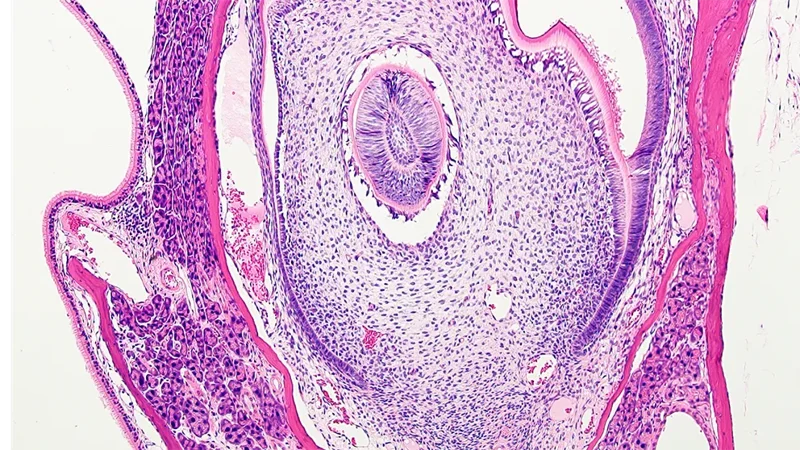

Histopathology Sciences (HPS) provides cutting-edge services enabling analysis of a wide range of anatomical, biochemical, protein, cell, and cell surface characteristics in tissue, blood, urine, and cerebrospinal fluid from various mouse models. The results are critical for numerous and varied phenotyping studies, monitoring disease progression, and determining response to drug treatments or effects of environmental factors. For example, investigators using mouse models of retinopathy rely on the work of HPS to identify lesions in the eye using both Histology and Electron Microscopy Services. The Histology and Clinical Chemistry Services partner with the JAX Diagnostic Program team and Clinical Pathologists to safeguard the health of JAX mouse colonies through the JAX colony monitoring program. The Histology and Electron Microscopy Services can also process fixed human tissue or cultured cell samples, patient-derived xenografts, and non-mammalian vertebrate samples. Our managers and experienced staff are available for consultation. Working together, they provide experimental design support and establish workflows to ensure that investigators can obtain the clearest results for their research.